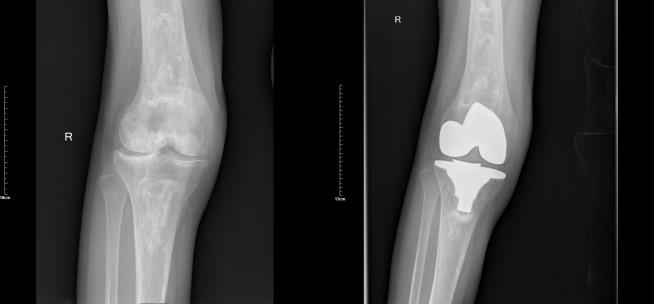

在智能医疗展示区,省四医院骨科团队带来的“机器人辅助关节置换技术”成为焦点。刘斌介绍,作为 2023年获批的省级临床重点专科,医院骨科紧跟技术前沿,2022年12月便与四川大学华西医院专家合作,成功开展我国自主研发辅助关节置换机器人上市后的全国首台膝关节置换术,标志着医院骨科迈入“精准化、智能化、个性化、微创化”诊疗新时代。

展会现场通过手术视频、3D模型演示、数据对比等形式,详细介绍了机器人辅助手术的技术优势:基于3D智能重建技术可个性化定制手术方案,操作精度达亚毫米级,机械臂稳定操作能有效减少组织损伤,使患者术中出血量降低40%、平均住院时间缩短30%,术后当天即可下床活动。目前,医院已成功开展机器人辅助关节置换手术近300例,手术成功率100%,平均手术精度误差小于1°,无严重并发症,患者术后满意度达98%以上,相关成果充分彰显医院在骨科智能手术领域的国内领先水平。据骨科团队介绍,未来医院还将拓展机器人辅助脊柱手术等新领域,让更多患者享受技术革新带来的优质医疗服务。